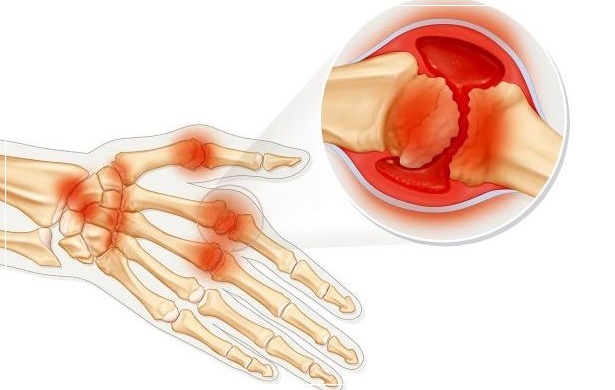

류마티스 관절염은 관절을 정상적으로 매끄럽게 하는 세포(활액 조직)에 영향을 주는 것입니다. 이것은 즉 다발성 관절, 보통 몸의 양쪽 편 모두에 영향을 주게 됩니다. 관절을 싸고 있는 막(활액낭)에 염증이 일어나고 부종이 발생하며 연골과 뼈는 부식됩니다. 부종이 발생한 조직은 주위 뼈를 연결시키는 결합조직인 인대를 신장시킬 수 있고 결과적으로 변형과 장애를 일으킬 수 있습니다.

초반에는 식욕부진, 피로감, 우울 등을 동반하기 때문에 단순한 감기로 오해할 수 있으니 주의가 필요합니다. 류마티스 관절염이 있다면, 면역력에 영향을 주는 담배는 절대 금물입니다. 초기에 치료하지 않으면 대부분의 환자가 1~2년 이내에 손가락 변형 등 심각한 관절 손상을 겪게 됩니다. 그러니 감기와 유사한 증상에 손가락 마디 통증이 더해진다면 빠른 시일 내에 병원을 찾는 것이 좋습니다.